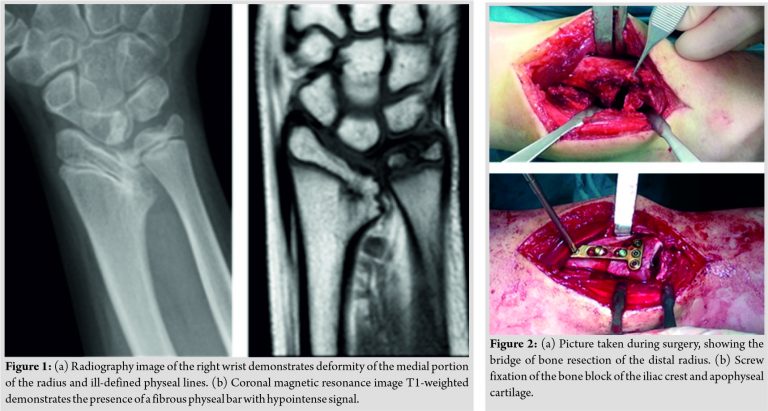

A 10-year-old boy with a history of right distal radius trauma without medical attention that came at our service 2 years later because of a progressive deformity of the wrist; he has not previous image studies. Radiography on admission showed a marked deformity at the medial border of the right distal radius at the level of the distal radioulnar joint due to the formation of a small bony bridge between epiphysis and metaphysis at the site of fracture (Fig. 1). Physical examination revealed the limitation of pronation/supination of the forearm. Neurologic and vascular examination was unremarkable.

Magnetic resonance image sequence demonstrates the presence of fibro-osseous physeal bar with hypointense signal, besides angular deformity of the radius.

When the boy was 12 years old, the bone bridge was resected and replaced with an autologous block from the apophyseal cartilage of iliac crest. The cartilaginous transplant was oriented such as the side of the graft closer to the bony iliac crest was placed in direct contact with the metaphysis of the radius. The angular deformity was corrected by an osteotomy followed by plate fixation (Fig. 2).